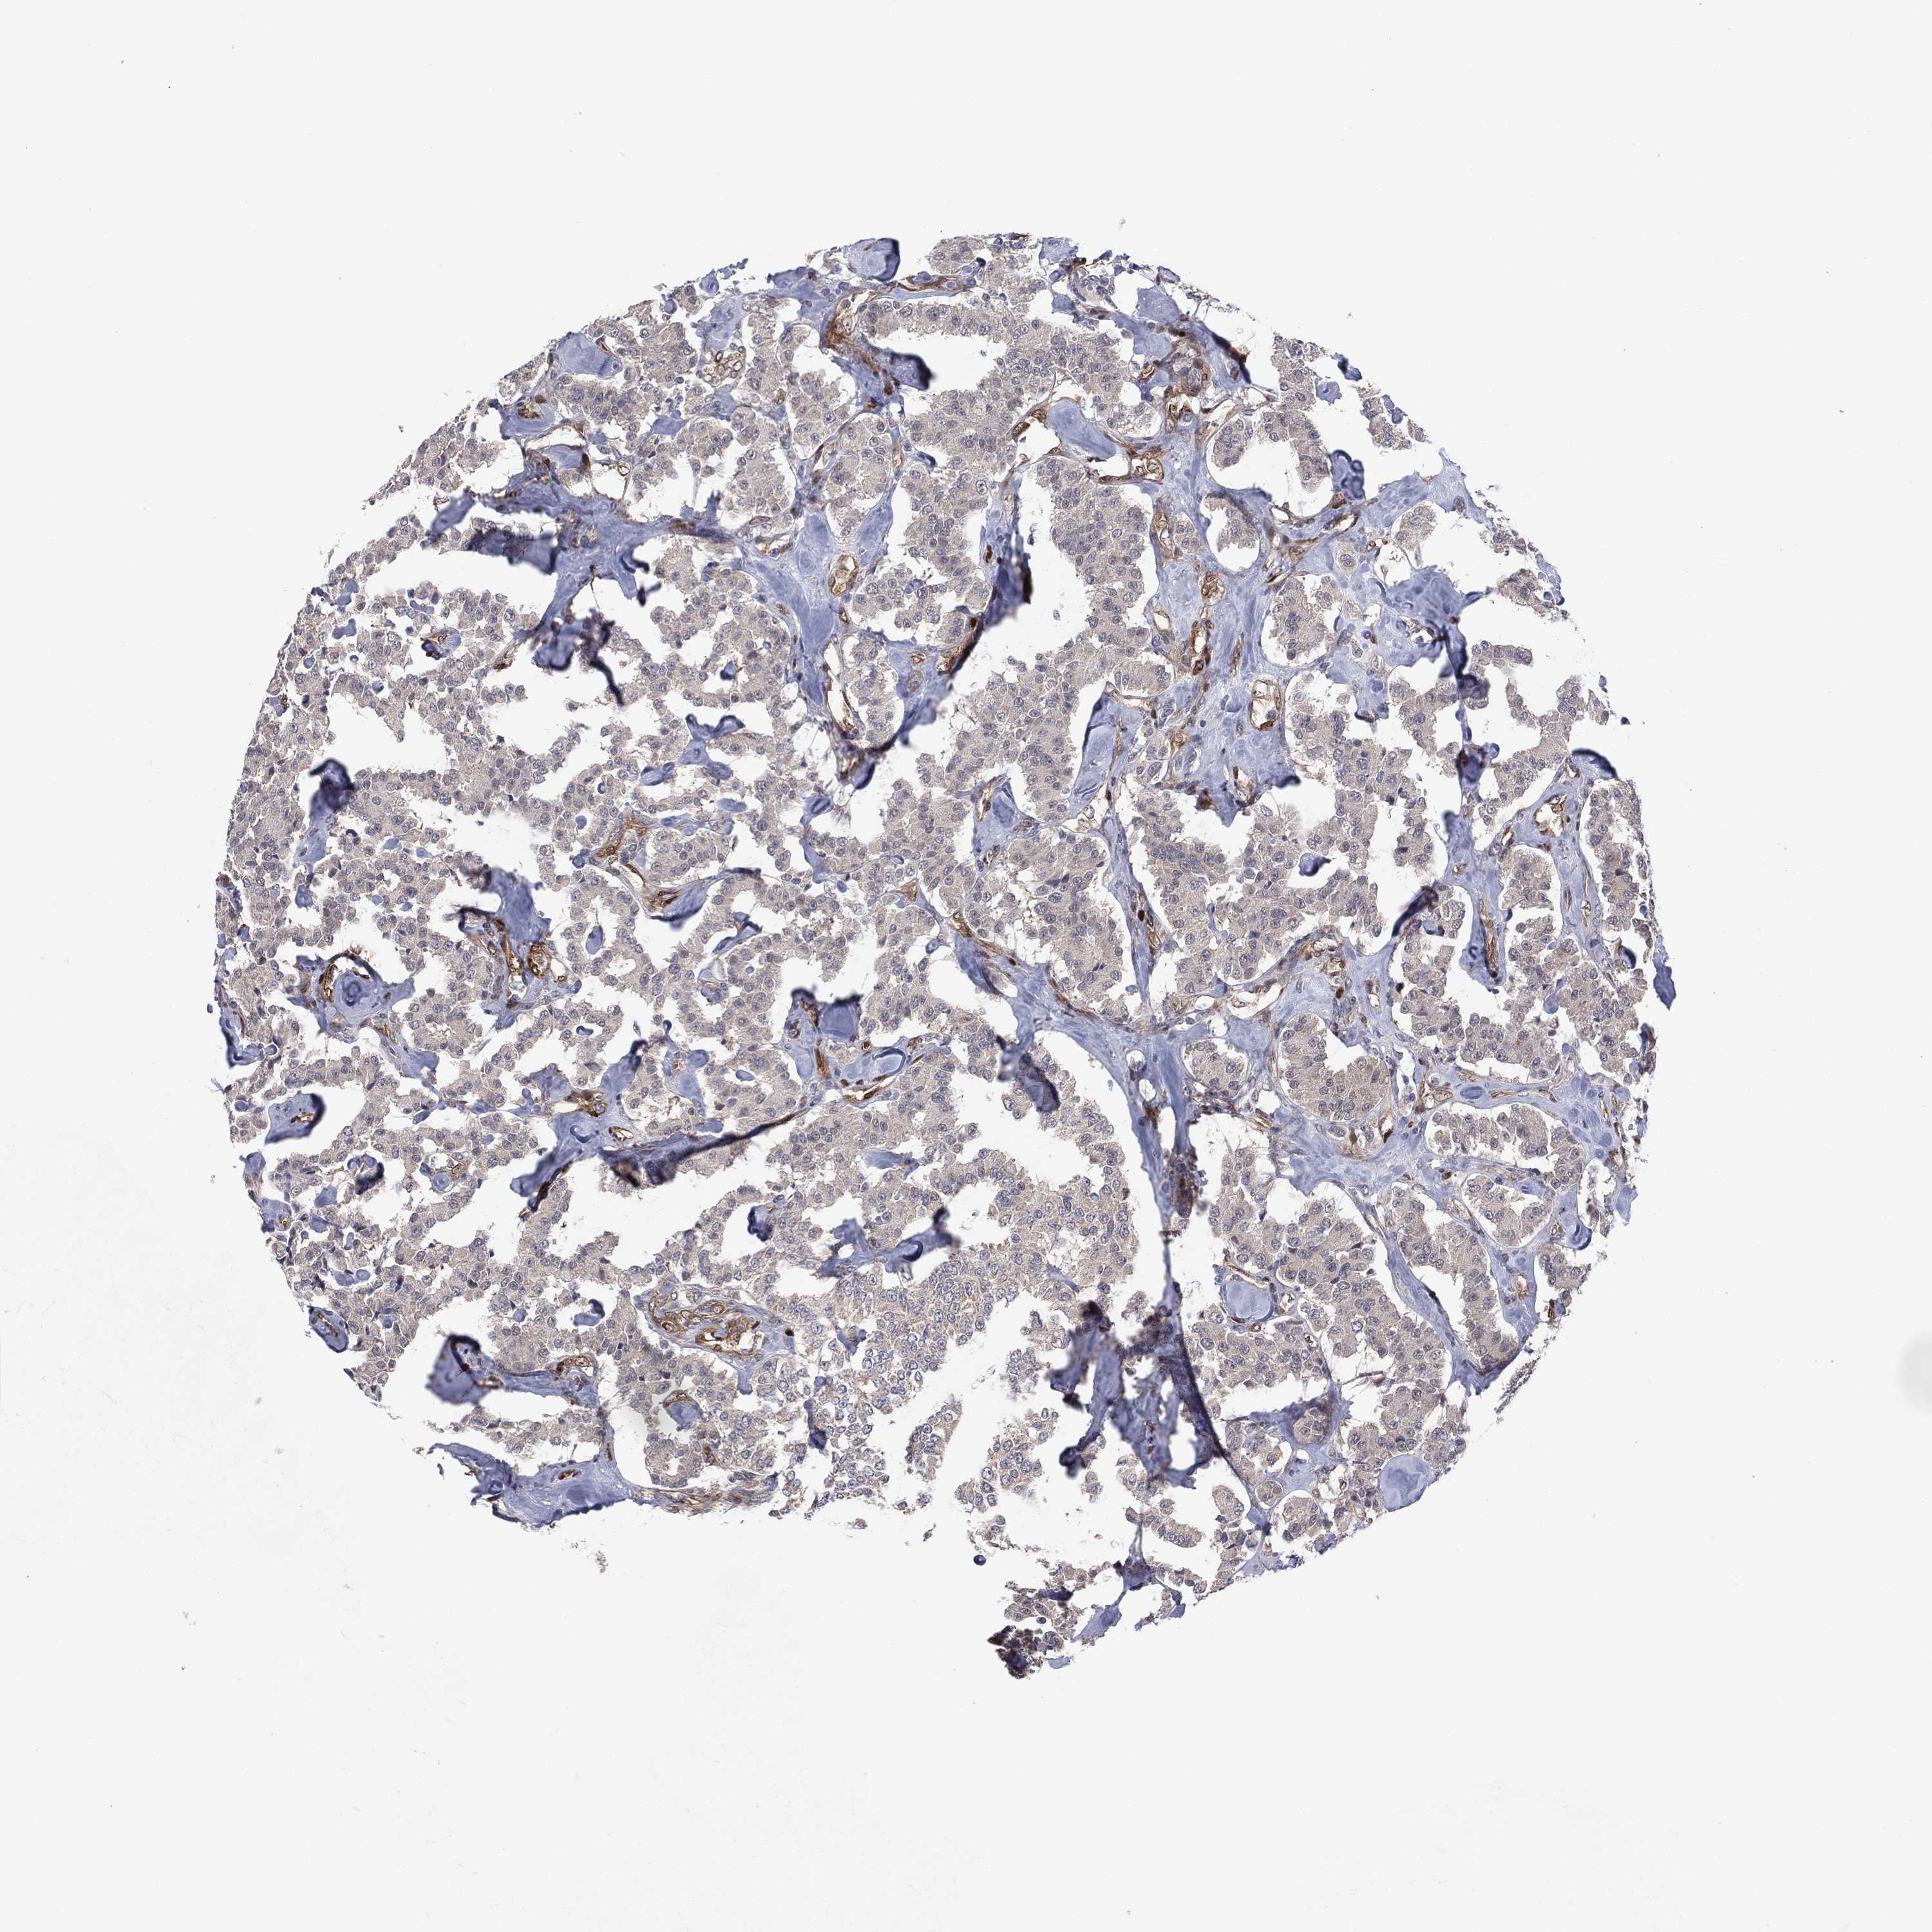

CARCINOID - Protein expressioni

A mouse-over function shows sample information and annotation data. Click on an image to view it in a full screen mode. Samples can be filtered based on level of antibody staining by selecting one or several of the following categories: high, medium, low and not detected. The assay and annotation is described here.

Antibody stainingi

Antibody staining in the annotated cell types in the current human tissue is reported as not detected, low, medium, or high, based on conventional immunohistochemistry profiling in selected tissues. This score is based on the combination of the staining intensity and fraction of stained cells.

Each image is clickable and will lead to virtual microscopy that enables deeper exploration of all samples and also displays staining intensity scores, fraction scores and subcellular localization as well as patient and tissue information for each sample.

Antibody CAB040581

Staining

High

Medium

Low

Not detected

Intensity

Strong

Moderate

Weak

Negative

Quantity

>75%

75%-25%

<25%

None

Location

Nuclear

Cytoplasmic/membranous

Cytoplasmic/membranous,nuclear

Carcinoid, malignant, NOS

Carcinoma, NOS